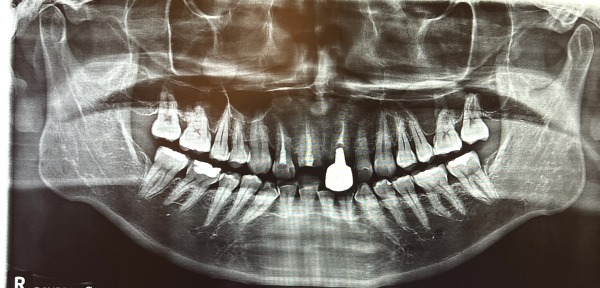

診察をしたところ、右上の差し歯は被せ物と一緒に歯が折れていましたが、幸いにも、歯根が割れていないことがわかりました。外れた差し歯の隣もすでに神経がなく、灰色に変色していました。患者様は、これを機に、右上2本を被せなおしたいとのご希望でした。

2日目〜5日目 右上1番の根管治療を行い、土台を立てました。

6日目〜7日目 右上2番の根管治療を行い、土台を立てました。